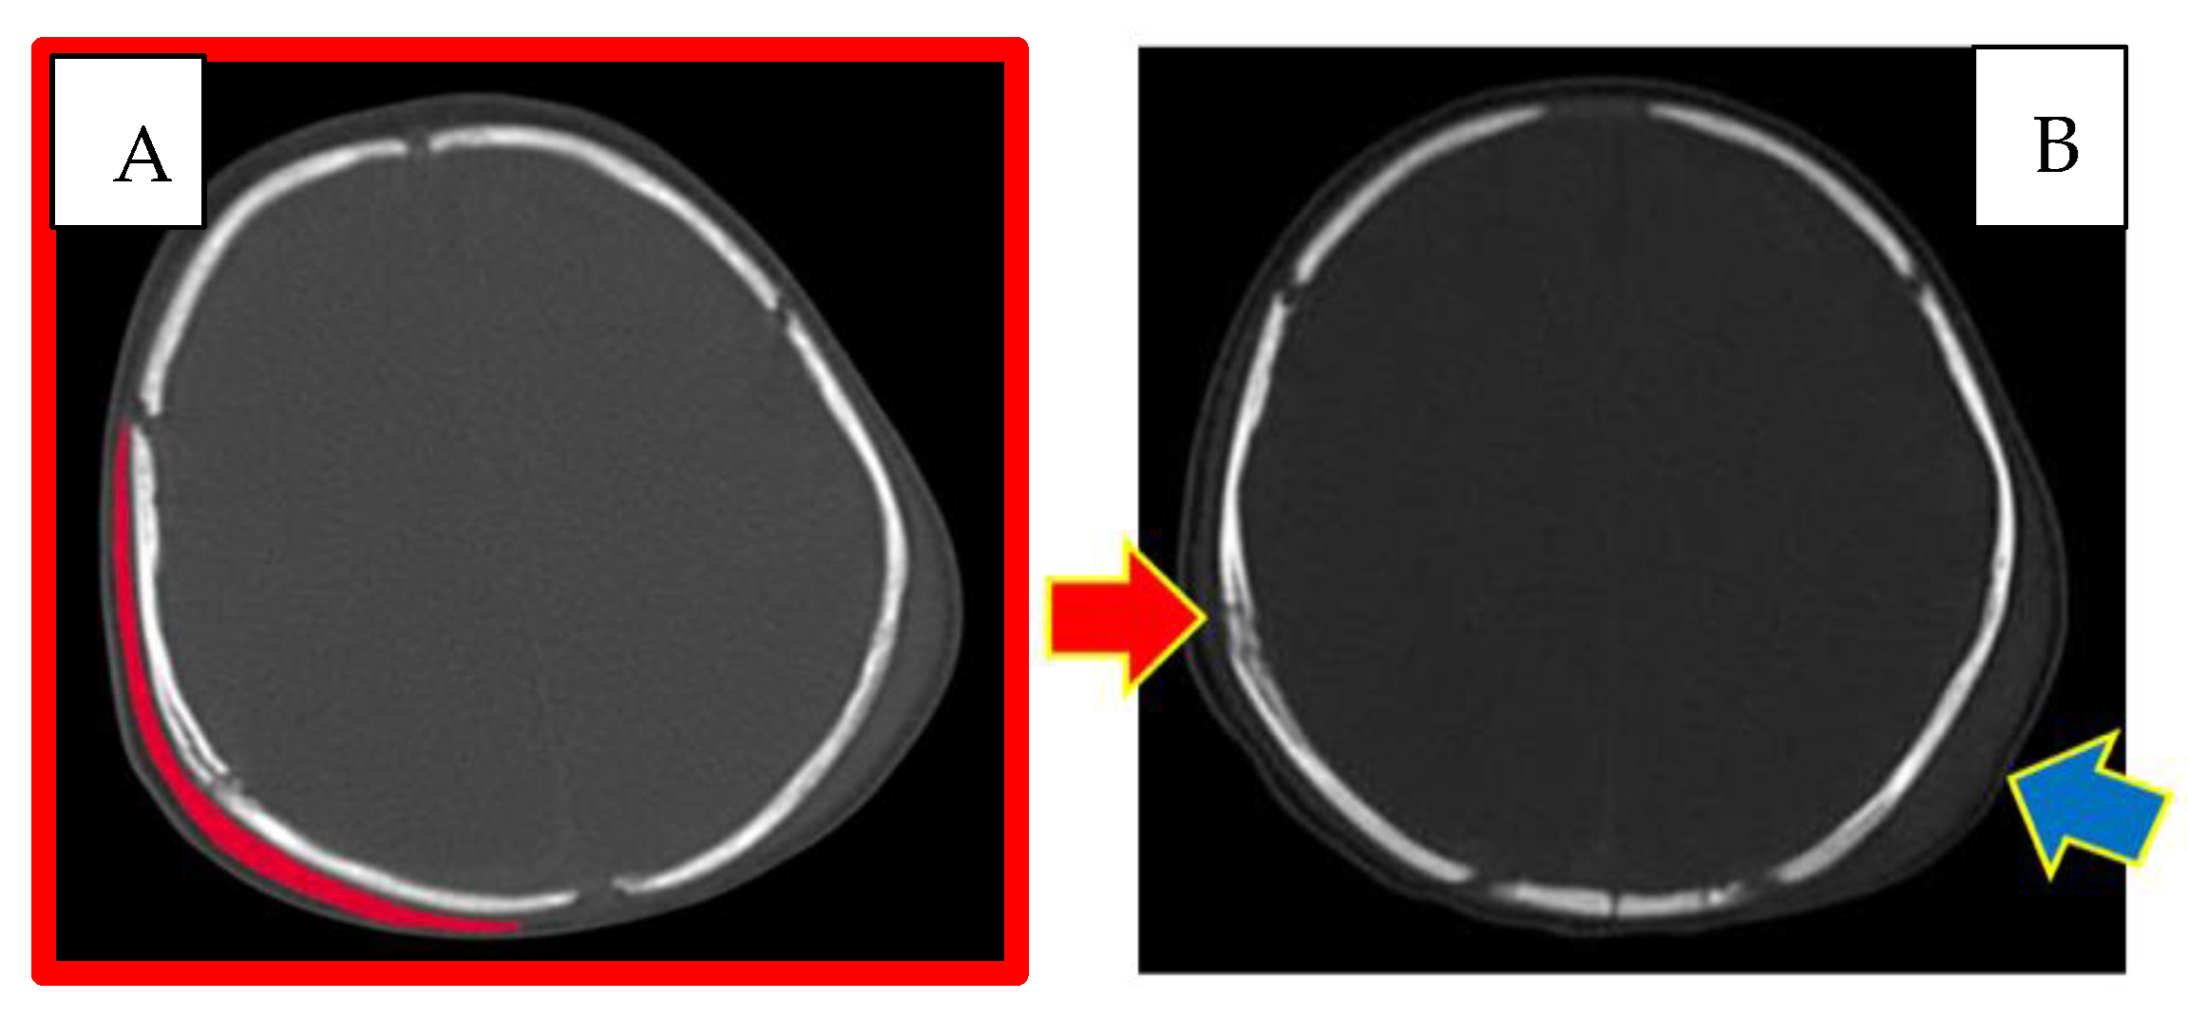

Figure 3.

CT skull. (A) Right subgaleal haematoma. (B) Red arrow: right parietal bone diploe involvement and consensual subgaleal haematoma; blue arrow: left subgaleal haematoma.

The appearance and extent of the haematomas were highlighted bilaterally, and the characteristics of the radiological images suggested that they may have appeared at the same time.